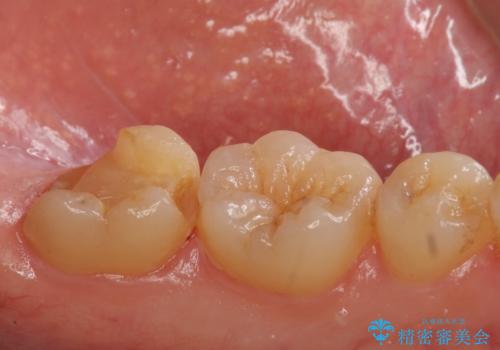

二つの提案をしたところ、①を選択されたのでゴールドインレーによる治療を行いました。

- ゴールドインレー 11万円費用は治療当時の料金となります

ゴールドインレーは歯質との適合がよく

虫歯の再発リスクや割れるというリスクが低いです。

しかしご自身での口腔内ケアを怠っていると虫歯の再発リスクは高くなるので

定期的にメンテナンスにくることをお勧めします。